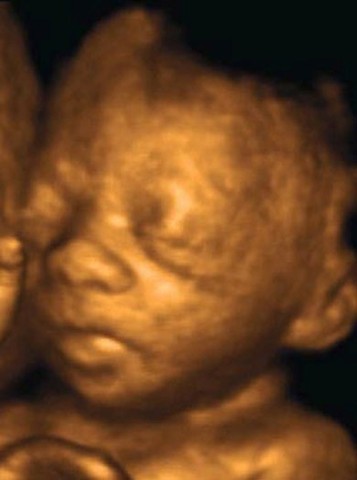

• week 12

week 12

The baby now has devolped facial features, such as a chin, nose, their facial profile, tooth buds. Their brain has fully devolped. Their vocal chords are now complete and they at times cry silently. The baby's eye lids are closed and will be until 7 months to protect the optical nerve. The fingers and toes have devloped soft nails and delicate hairs are beginning to grow on their heads. The baby's head makes up about half of the fetus size.

http://www.babycentre.co.uk/12-weeks-pregnant